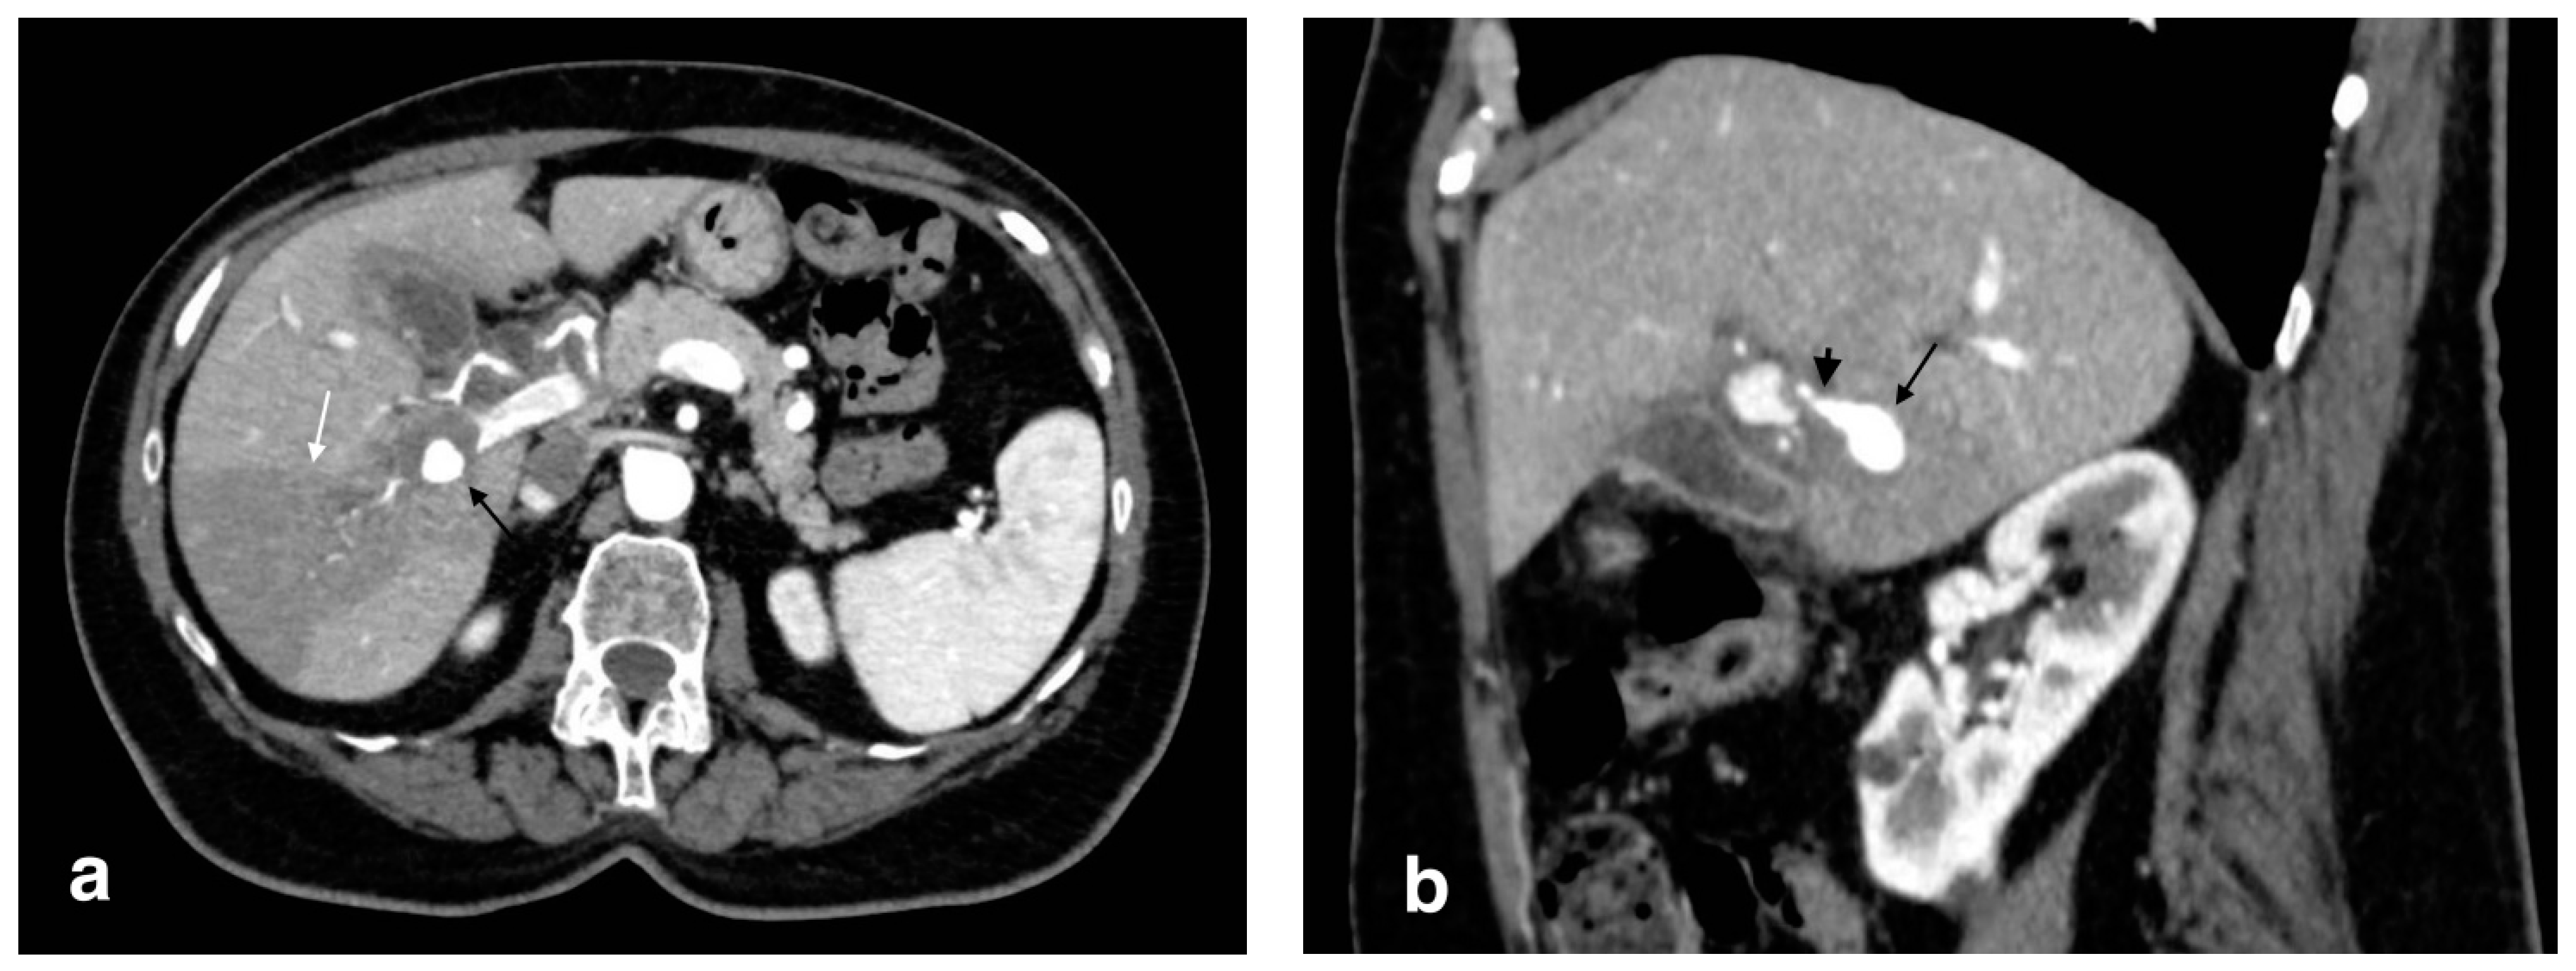

Figure 10.

Right portal vein thrombosis: extensive right portal vein hypodensity subsequent to an intraluminal thrombus formation (black arrows) with hepatic hyperemia (white arrows).